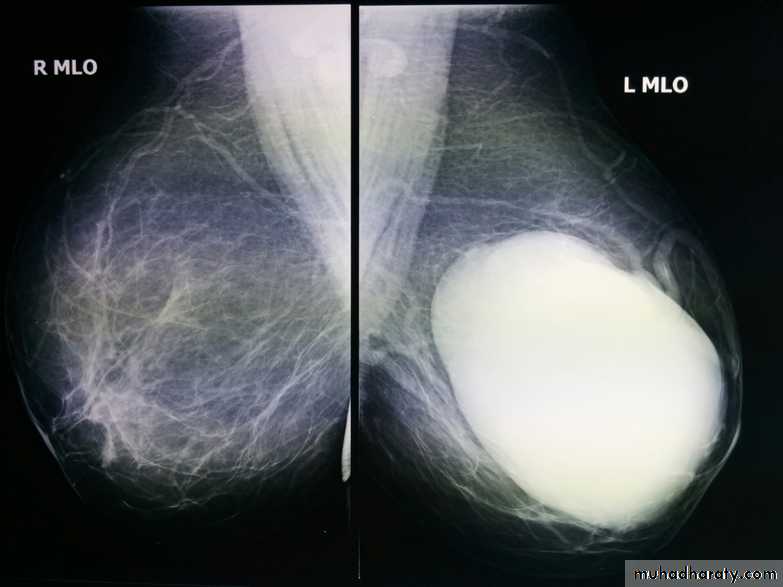

The mediolateral oblique (MLO) view is one of standard mammographic views. It is the most important projection as it allows to depict most breast tissue.The craniocaudal view (CC view), is one of the two standard projections in a screening mammography. It must show the medial part as well the external lateral portion of the breast as much as possible.

ILC is more often multicentric and bilateral (10-15%). Therefore imaging evaluation of the contralateral breast is crucial. There can be very subtle changes such as progressive shrinkage or enlargement or reduced compressibility of the involved breast. Imaging often underestimates the disease.

Mammography

The sensitivity of mammography for the detection of ILC reportedly ranges between 55-80% 8. Because of the limitations of mammography in detecting ILC, other modalities, such as sonography and MR imaging, are being used in evaluating clinically suspicious findings and known cancers to assess the extent of disease. ILC are more commonly seen on the craniocaudal (CC), compared to the mediolateral oblique (MLO).